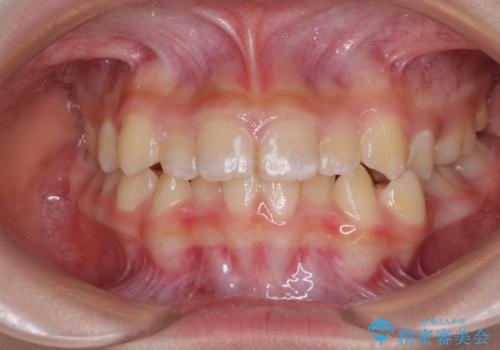

- 小児矯正の頃から診察を行っている患者様です。

上顎骨の幅が下顎骨よりも小さいので、拡大装置により骨幅を広げて上下関係を改善し、その後インビザラインにて歯並びを整えることとしました。

上下の骨幅を改善したことで、スムーズに歯列矯正を行うことができました。